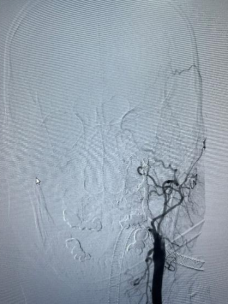

由于内镜下止血困难,考虑鼻咽癌治疗后并发颈内动脉爆裂综合征大出血,治疗团队立即将患者转入复合手术室。此时,神经外科脑血管病团队早已枕戈待旦,无缝衔接开始手术。面对患者大出血的危急情况,神经外科昝春树主治医师来不及穿戴铅衣,一头扎进抢救工作。股动脉穿刺,微导管、超滑导丝导引导管迅速超选至左侧颈内动脉等系列操作一气呵成。术中造影证实了左侧颈内动脉假性动脉瘤破裂出血,像一股洪流一样持续向外喷出。

箭头所指为出血点